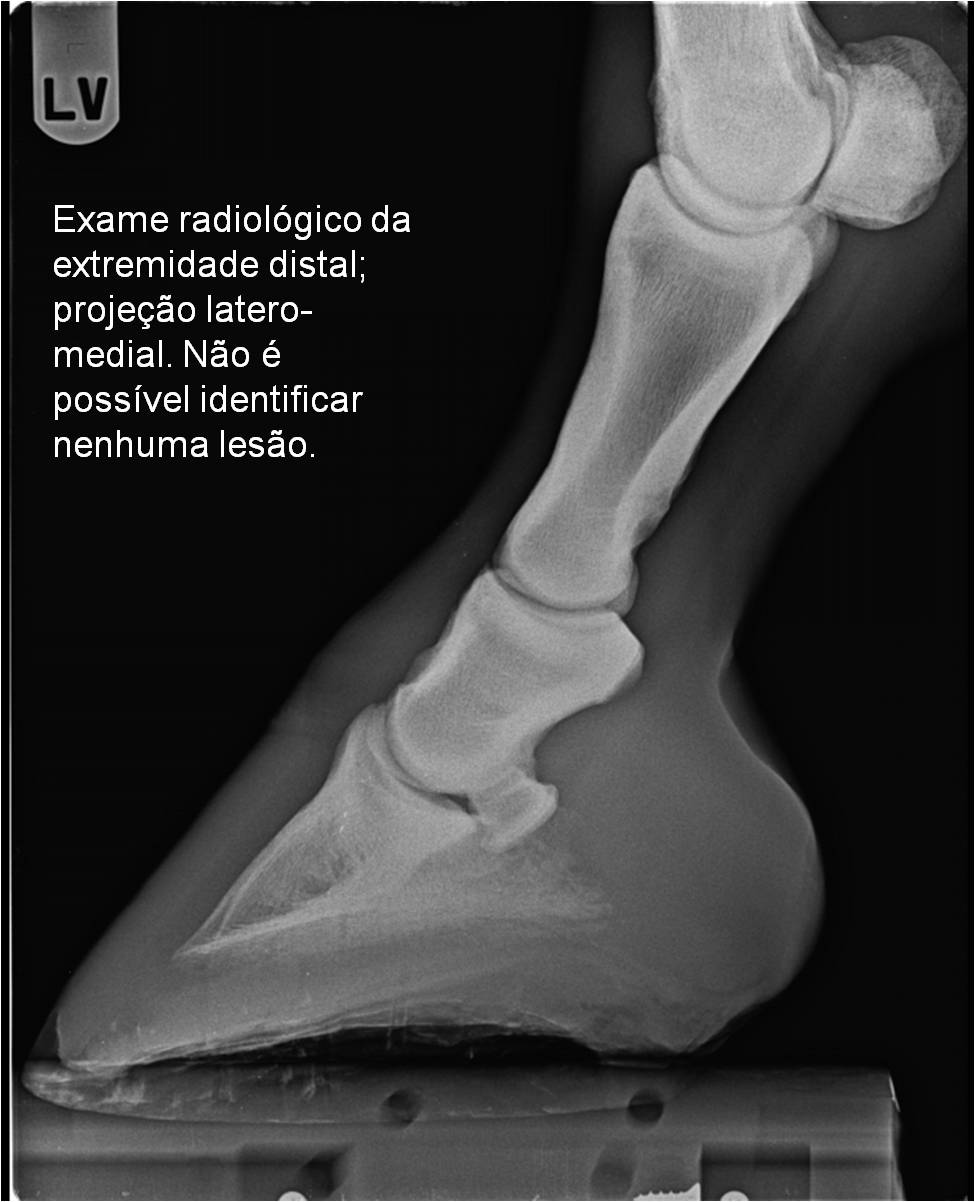

Publisher: Universidade de Évora

Abstract: O relatório de estágio encontra-se estruturado em três partes distintas. A primeira parte faz a caracterização das infraestruturas e funcionamento do Hospital Veterinário de Equinos de Lüsche, Oldenburg, Alemanha, assim como a análise casuística dos casos clínicos acompanhados durante os 6 meses de estágio. A segunda parte consiste de uma revisão bibliográfica sobre quistos do osso subcondral em equinos. Por fim, a terceira parte consta da apresentação e discussão de um caso clínico, nomeadamente o diagnóstico e acompanhamento imagiológico, por ressonância magnética, de um quisto subcondral na terceira falange num cavalo adulto; ### Abstract Equine Practice- Subcondral bone cyst of the third phalanx This internship report is divided in three parts. The first part characterizes the infrastructure and function of the Equine Hospital Lüsche, Oldenburg, Germany, as well as the casuistic of the clinical cases accompanied during the 6 month internship. The second part consists in a bibliographic review of cystic lesions of the subchondral bone in equines. The third part consists in a case report, the diagnostic and imagiological accompaniment, by use of magnetic resonance imaging, of a subchondral bone cyst in the distal phalanx of an adult equine.